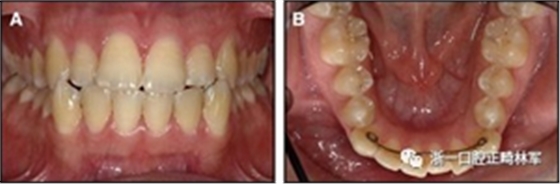

隨著時(shí)間的推移,全維度弓絲及其表達(dá)的牙齒間扭矩差異顯著改善(圖17)。明智的鄰間減少之后,間隙關(guān)閉擴(kuò)大接觸面,消除不美觀的黑三角。在脫粘之前也校正了牙齒排列和牙弓形態(tài)(圖18)。

之前和之后的三維圖像(圖19)突出顯示在下頜右側(cè)尖牙面?zhèn)缺砻嫔瞎堑脑黾右约扒把姥栏恢玫母纳啤S捎谙骂M切牙的伸長(zhǎng)被認(rèn)為是不嚴(yán)謹(jǐn)?shù)?,因此輕度前牙開(kāi)合沒(méi)有被矯正。

圖18.脫粘后的最終圖像:A,正面視圖; B,咬合面視圖。 進(jìn)一步的牙齒移動(dòng)以糾正輕度前牙開(kāi)合被認(rèn)為不符合患者的最佳利益。